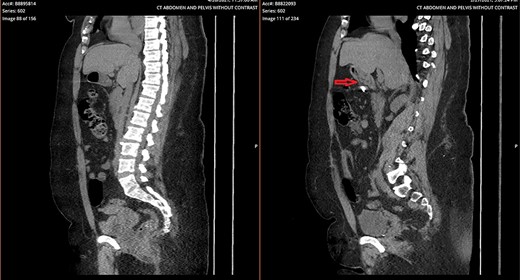

A 43-year-old incarcerated woman with borderline personality disorder and a long history of swallowing various foreign objects in periods of stress presented to the emergency department after swallowing a cup of bleach. Her surgical history was significant for multiple celiotomies for retrievals of purposefully ingested foreign bodies. During evaluation, she also admitted to swallowing an ink pen 3 weeks prior to swallowing the bleach for which she did not seek medical evaluation. She reported no food intolerance or changes in bowel function secondary to swallowing these objects. She presented with mild abdominal pain and cramping, and her vital signs and laboratory investigations were all within normal limits. Her abdominal exam was notable for mild tenderness to palpation diffusely. Computed tomography (CT) of the abdomen (Fig. 4) showed a linear foreign body in the distal gastric antrum penetrating the inferior wall and extending into the adjacent peritoneal fat. No free air or free fluid was appreciated. Initial esophagogastroduodenoscopy (EGD) was significant for mild erythema and edema to the esophageal and duodenal mucosa as a result of the caustic ingestion, and the pen was found to be deeply perforating the stomach antral wall with no associated ulcer or edema (Fig. 1). The depth at which the foreign body was lodged was uncertain, so there was concern for organ involvement outside of the gastric wall. Repeat EGD was done to assess for manifestations of esophageal, gastric or duodenal injuries from her caustic ingestion, and it revealed normal gastric mucosa (Fig. 2). A joint case was planned with the gastroenterology service for endoscopic foreign body retrieval, possible laparoscopic retrieval and gastric repair and possible open retrieval and gastric repair. The patient was taken to the operating room for the third EGD, which revealed spontaneous migration of the foreign body from the perforation site into the lumen of the gastric body (Fig. 3a). Additionally, there was spontaneous closure of the site of previous perforation (Fig. 3b and c). The ink pen was easily removed transorally using an endoscopic snare, and no further surgical intervention was required. After the procedure, the patient reported complete resolution of her abdominal pain and was able to tolerate a regular diet without problems.

Side-by-side comparison of foreign body perforating through stomach (right) and sealed site of perforation after endoscopic removal (left).